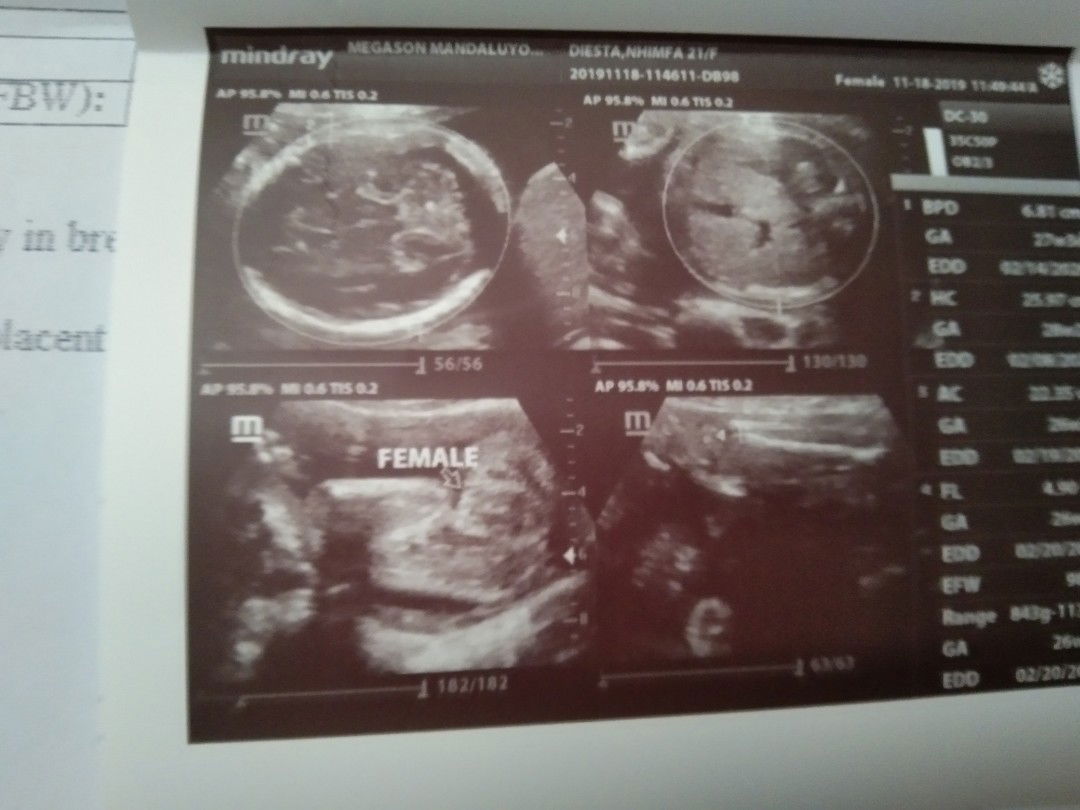

#Hello ma' little princess????